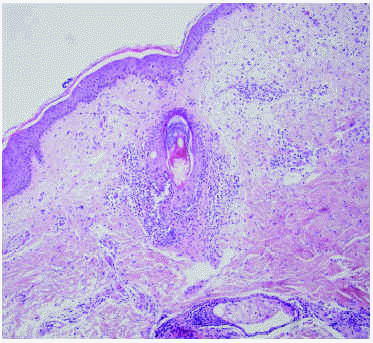

Se realizó una biopsia de una de las lesiones del tórax, donde se observaba un denso infiltrado neutrofílico, con células linfohistocitarias alrededor y en el seno de los folículos pilosos, con formación de pústulas en las zonas más superficiales de éstos (fig. 4). El diagnóstico histológico fue foliculitis aguda pustulosa. Asimismo, se tomó una muestra para cultivo bacteriano de una de las lesiones pustulosas, en la que creció Staphylococcus epidermidis.

Fig. 4.--Histología: infiltrado neutrofílico y linfohistiocitario alrededor del folículo piloso, con formación de pústula superficial. (Hematoxilina-eosina, x20.)